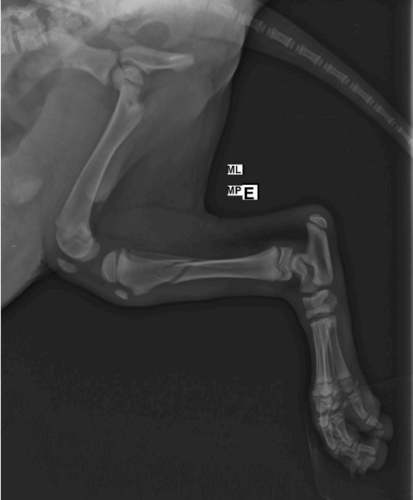

Nosso filhotinho ainda com a tala temporária para minimizar a dor.Muito obrigado pelo apoio! Com a sua ajuda, logo ele estará correndo e brincando novamente. 💕🐾